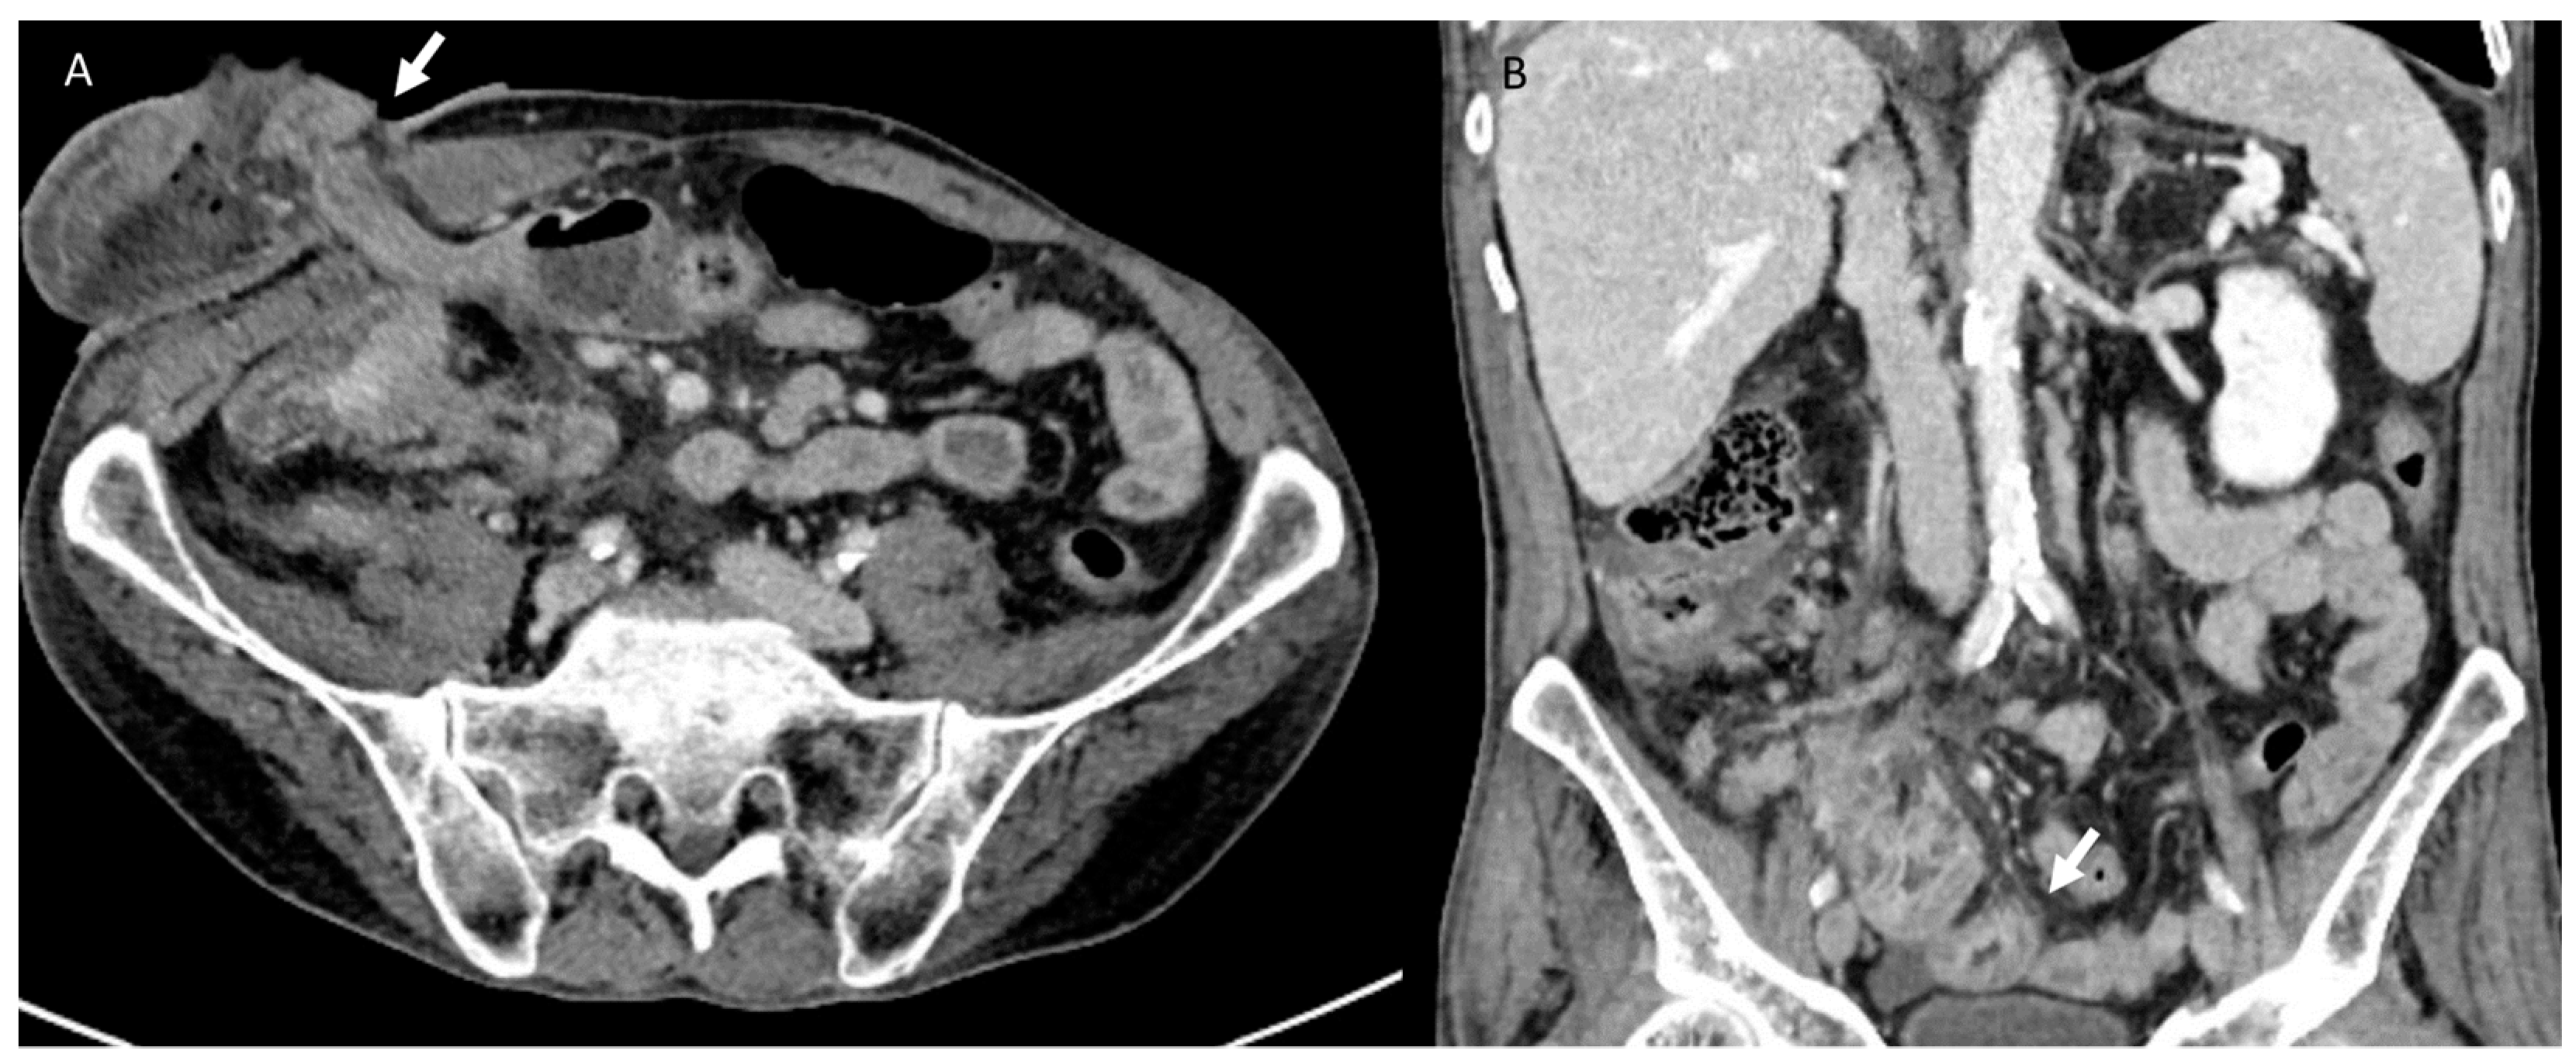

3.3. Bleeding

3.4. Urological Injury

3.5. Wound Infections

3.6. Hernia

3.7. Local Recurrence